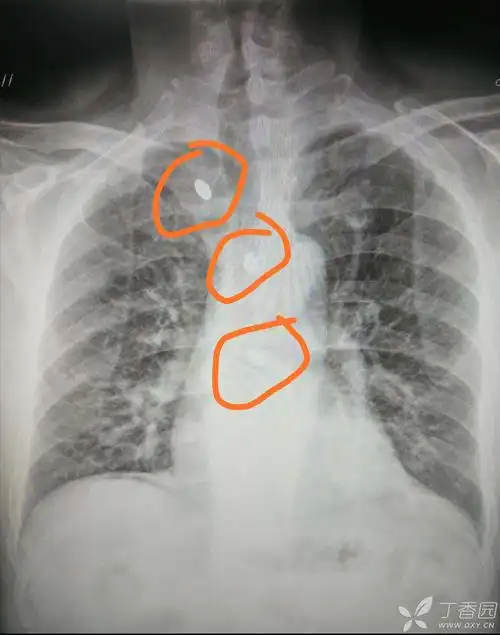

【影像读片】一张正位胸片,看看考虑什么(结果已公布)

点击图片查看原图